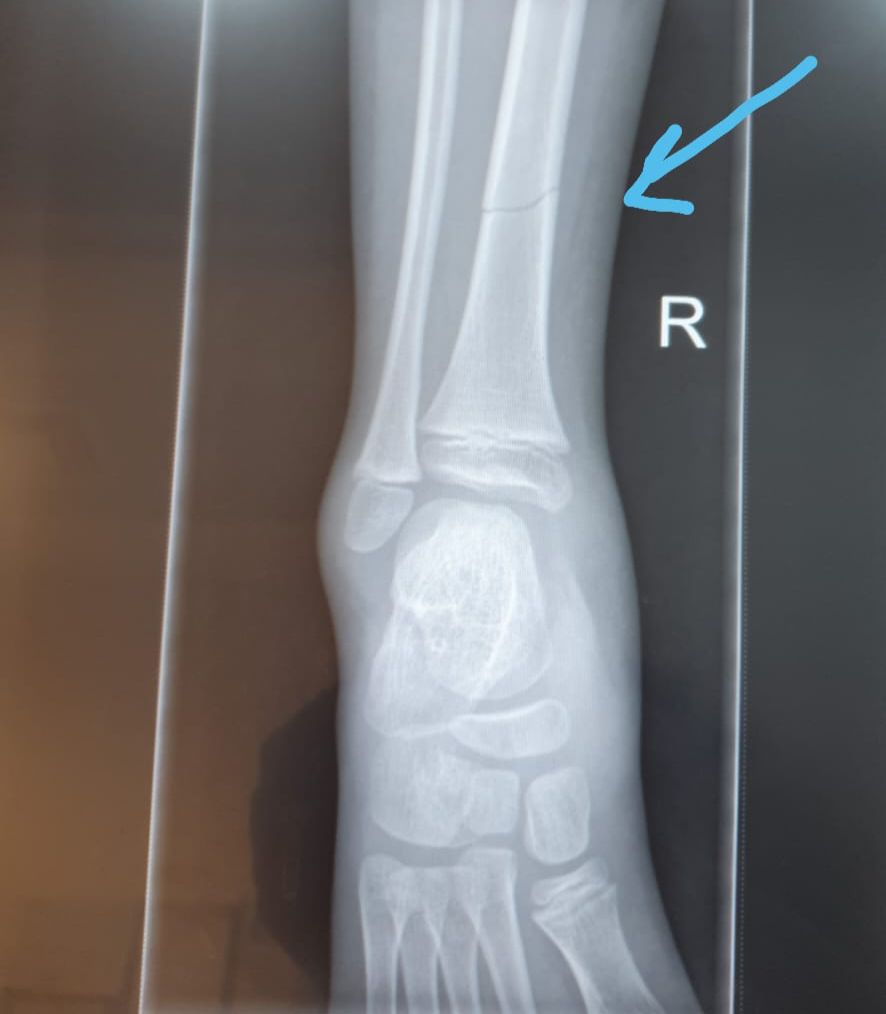

בתחילת השבוע הגיע למוקד נער כבן 14, עם כאבים עזים ברגלו, בתוך כשעה הספיק צוות האורתופדיה המיומן לאבחן ולגבס שבר ברגלו שלא אותר בבדיקה במקום אחר, הנער טופל, נמנע ממנו עוד כאב וסבל מיותר וזוהי עוד דוגמא מיני רבות..